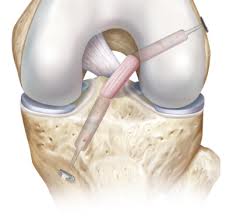

אין לי רצועה צולבת! מאמר שני בסדרת ניתוחים על שולחן הניתוחים